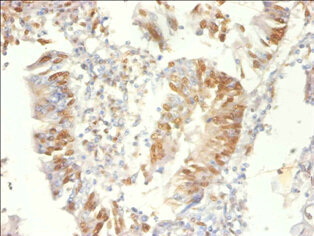

Immunohistochemistry of paraffin-embedded human colon cancer using CSB-PA13674A0Rb at dilution of 1:100